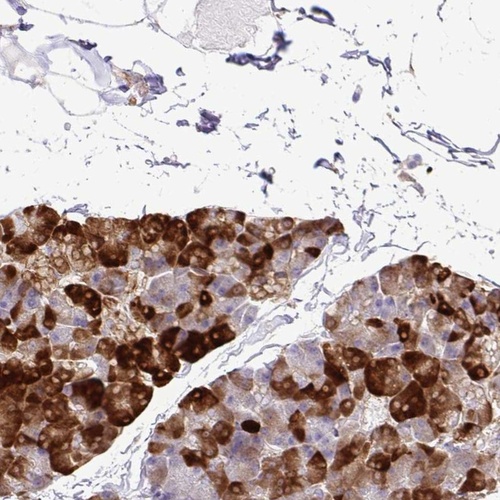

Immunohistochemical staining of human pancreas shows strong cytoplasmic positivity in exocrine glandular cells.